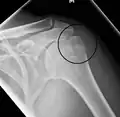

A fracture of the greater tuberosity as seen on AP X ray -

A fracture of the greater tuberosity of the humerus -

Fracture of the greater tuberosity of the humerus -

Definitive diagnosis of humerus fractures is typically made through radiographic imaging. For proximal fractures, X-rays can be taken from a scapular anteroposterior (AP) view, which takes an image of the front of the shoulder region from an angle, a scapular Y view, which takes an image of the back of the shoulder region from an angle, and an axillar lateral view, which has the patient lie on his or her back, lift the bottom half of the arm up to the side, and have an image taken of the axilla region underneath the shoulder.[9] Fractures of the humerus shaft are usually correctly identified with radiographic images taken from the AP and lateral viewpoints.[12] Damage to the radial nerve from a shaft fracture can be identified by an inability to bend the hand backwards or by decreased sensation in the back of the hand.[5] Images of the distal region are often of poor quality due to the patient being unable to extend the elbow because of pain. If a severe distal fracture is suspected, then a computed tomography (CT) scan can provide greater detail of the fracture. Nondisplaced distal fractures may not be directly visible; they may only be visible due to fat being displaced because of internal bleeding in the elbow.[7]